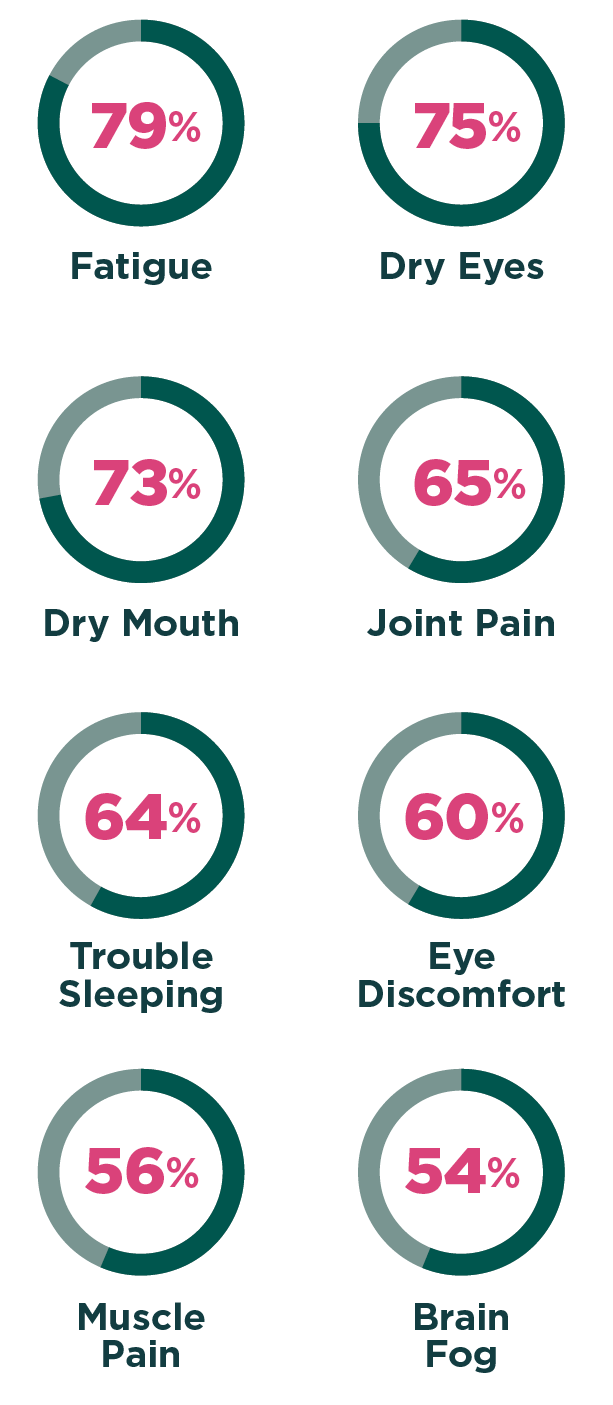

8 MOST IMPACTFUL SJOGREN’S SYMPTOMS

In 2021, The Harris Poll conducted a survey for the Sjogren’s Foundation that included 3,622 U.S. adults diagnosed with the disease.4 Among 48 symptoms experienced by participants, eight had a moderate to major impact on the majority of people.

These included:

Additionally, participants were also bothered by anxiety, depression, neuropathy, gastroesophageal reflux disease (GERD), vaginal dryness, tooth decay, diarrhea, headache/migraine and vision problems, among other symptoms.